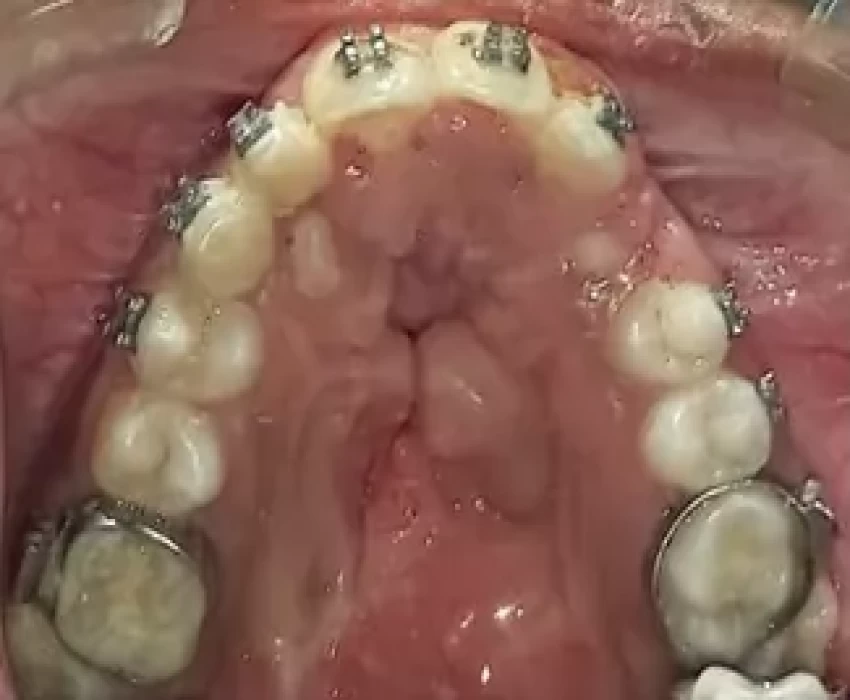

The anterior crossbite is sometimes difficult to correct.

Originally, acrylic bite blocks on the occlusal surface of the teeth are used to raise the bite for their correction.

Most of the time, the patient reports before the prescribed appointment with loose bite blocks and debonded brackets, thus delaying the treatment time. This technique involves fabrication of an acrylic bite block with the involvement of stainless steel wire for stability and correct placement of the block over the teeth.

Make an impression of the maxillary arch and prepare the working cast with the selection of the bands.

Take a round stainless steel wire (21 gauge) and form a triangle with its edges toward the cusp tip. Make a 90° horizontal bend and involve a helix of 3 mm in diameter for the ease to hold the block for insertion in the tube. Insert the wire in the auxiliary slot of the bands. Cut the excess wire than required.